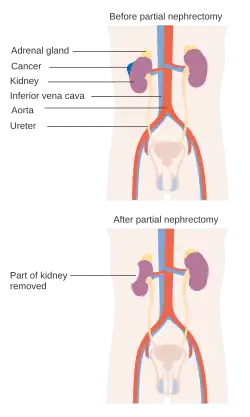

Before and after a partial nephrectomy | |

Partial nephrectomy is the surgical removal of a kidney tumor along with a thin rim of normal kidney, with the two aims of curing the cancer and preserving as much normal kidney as possible.

A partial nephrectomy should be attempted when there is a kidney tumor in a solitary kidney, when there are kidney tumors in both kidneys, or when removing the entire kidney could result in kidney failure and the need for dialysis.

Partial nephrectomy is also the standard of care for nearly all patients with small renal masses (<4 cm in size).[22] Most renal masses between 4-7 centimeters can also be treated by partial nephrectomy if they are located in the proper position.[23] Renal masses larger than 7 centimeters are generally treated with radical nephrectomy unless the tumor occurs in a solitary kidney, there are tumors on both sides or kidney function is bad. Patients who are told their tumors are too big or too hard for a partial nephrectomy may want to seek another opinion because surgeons who take care of many patients with kidney cancer are more often able to spare the kidney than those who only see a few cases.[24]

A partial nephrectomy is performed with a patient under general anesthesia as well. A partial nephrectomy can be performed through an open, laparoscopic[25] or robotic approach. The patient is typically placed on the operating room bed lying on the side opposite the kidney tumor. The goal of the procedure is to remove the kidney tumor along with a thin rim of normal kidney tissue. Because the kidneys clean the blood, all blood eventually flows through the kidneys and 25% of it will go into the kidneys with each heart beat. In order to safely remove the kidney tumor, the blood flow to the kidney is often temporarily blocked off. The tumor is then cut out and the surgeon must sew the remaining kidney back together. Partial nephrectomy is often an alternative to complete, or radical, nephrectomy for renal cell cancer.